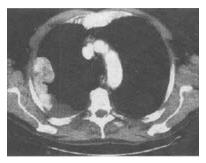

患者,男,54岁,胸痛1个月伴加重,CT如图,最可能的诊断是()。

A、淋巴瘤

B、右侧胸膜转移瘤

C、右侧胸膜间皮瘤

D、右侧胸膜增厚

E、右上肺不张伴胸膜增厚

C